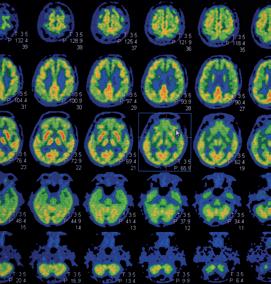

5.2 Medische beeldvorming 279